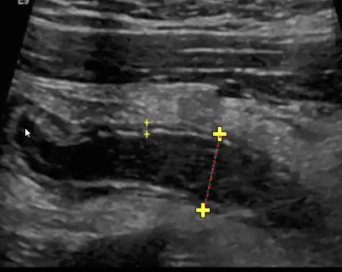

What is this and what type of scan

Polycystic kidney disease, US